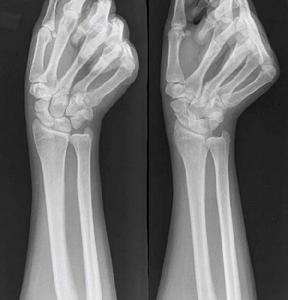

2.X線攝正側斜位片。有時早期骨折線顯示不清可在兩周后再攝片以便確診。

傷後局部腫脹,疼痛,腕關節活動受限並疼痛加重。鼻咽窩處及舟骨結節處有壓痛。第2、3掌骨頭縱向叩擊痛。有時輕微骨折症狀不明顯,與腕扭傷症狀相似,易誤診忽略,腕關節正位、側位、斜位(舟狀位)三種方位X片可確診骨折部位及方向。若骨折不清楚,臨床症狀懷疑骨折時,應暫按骨折處理,待二周后,複查X片。由於骨折處骨質吸收,骨折線能明顯認出。

傷後腕部橈側腫脹疼痛,腕關節活動時疼痛加劇並受限。鼻咽窩及舟骨結節處有明顯壓痛。腕關節橈偏,沿Ⅰ、Ⅱ掌骨長軸叩擊或擠壓時均引起骨折處疼痛。X線片需攝腕關節正、側位及舟骨位三個方向,多能顯示骨折線。有時沒有移位的骨折,早期X線片為陰性。對可疑病例,應在兩周后再照片複查,因傷後骨折處骨質吸收,骨折線增寬而顯出。陳舊性骨折,可見骨折線明顯增寬,骨折端硬化或囊性變,這是骨不連線的表現,若近段骨塊密度增加、變形等則為缺血性壞死。

舟骨骨折按骨折發生的部位分為舟骨中段骨折、近段骨折和結節部骨折。舟骨骨折的骨折線如錯位不明顯時,須留意下列可提示診斷的徵象:①舟骨結節的骨皮質斷裂;②舟骨結節部或頭舟關節間隙內的小游離骨折片;③舟骨一側或雙側關節面骨皮質出現中斷或有垂直於關節面的細小裂隙、皺摺、台階樣改變。